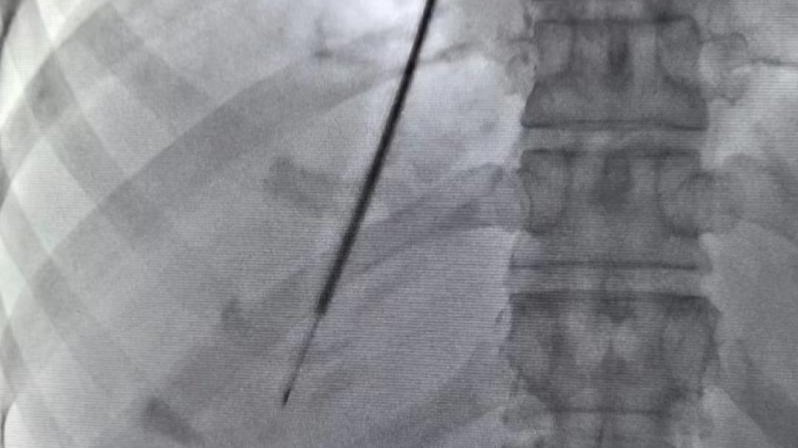

近日,新疆医科大学第一附属医院感染病·肝病中心三科联合介入放射科,首次在疆内成功开展“经颈静脉肝内活检术(TJLB)”技术。该技术通过微创的方法为不明原因的疑难危重肝病患者进行肝组织活检,通过获得满意的肝组织标本为患者提供明确诊断,及时给予患者更加有针对性的诊疗方案,帮助患者转危为安。经颈静脉肝内活检术(X光下)当前,肝脏病理检查是临床中用以诊断疑难、复杂肝病的主要手段,而最常用的获得肝组织标本的....查看详情 >